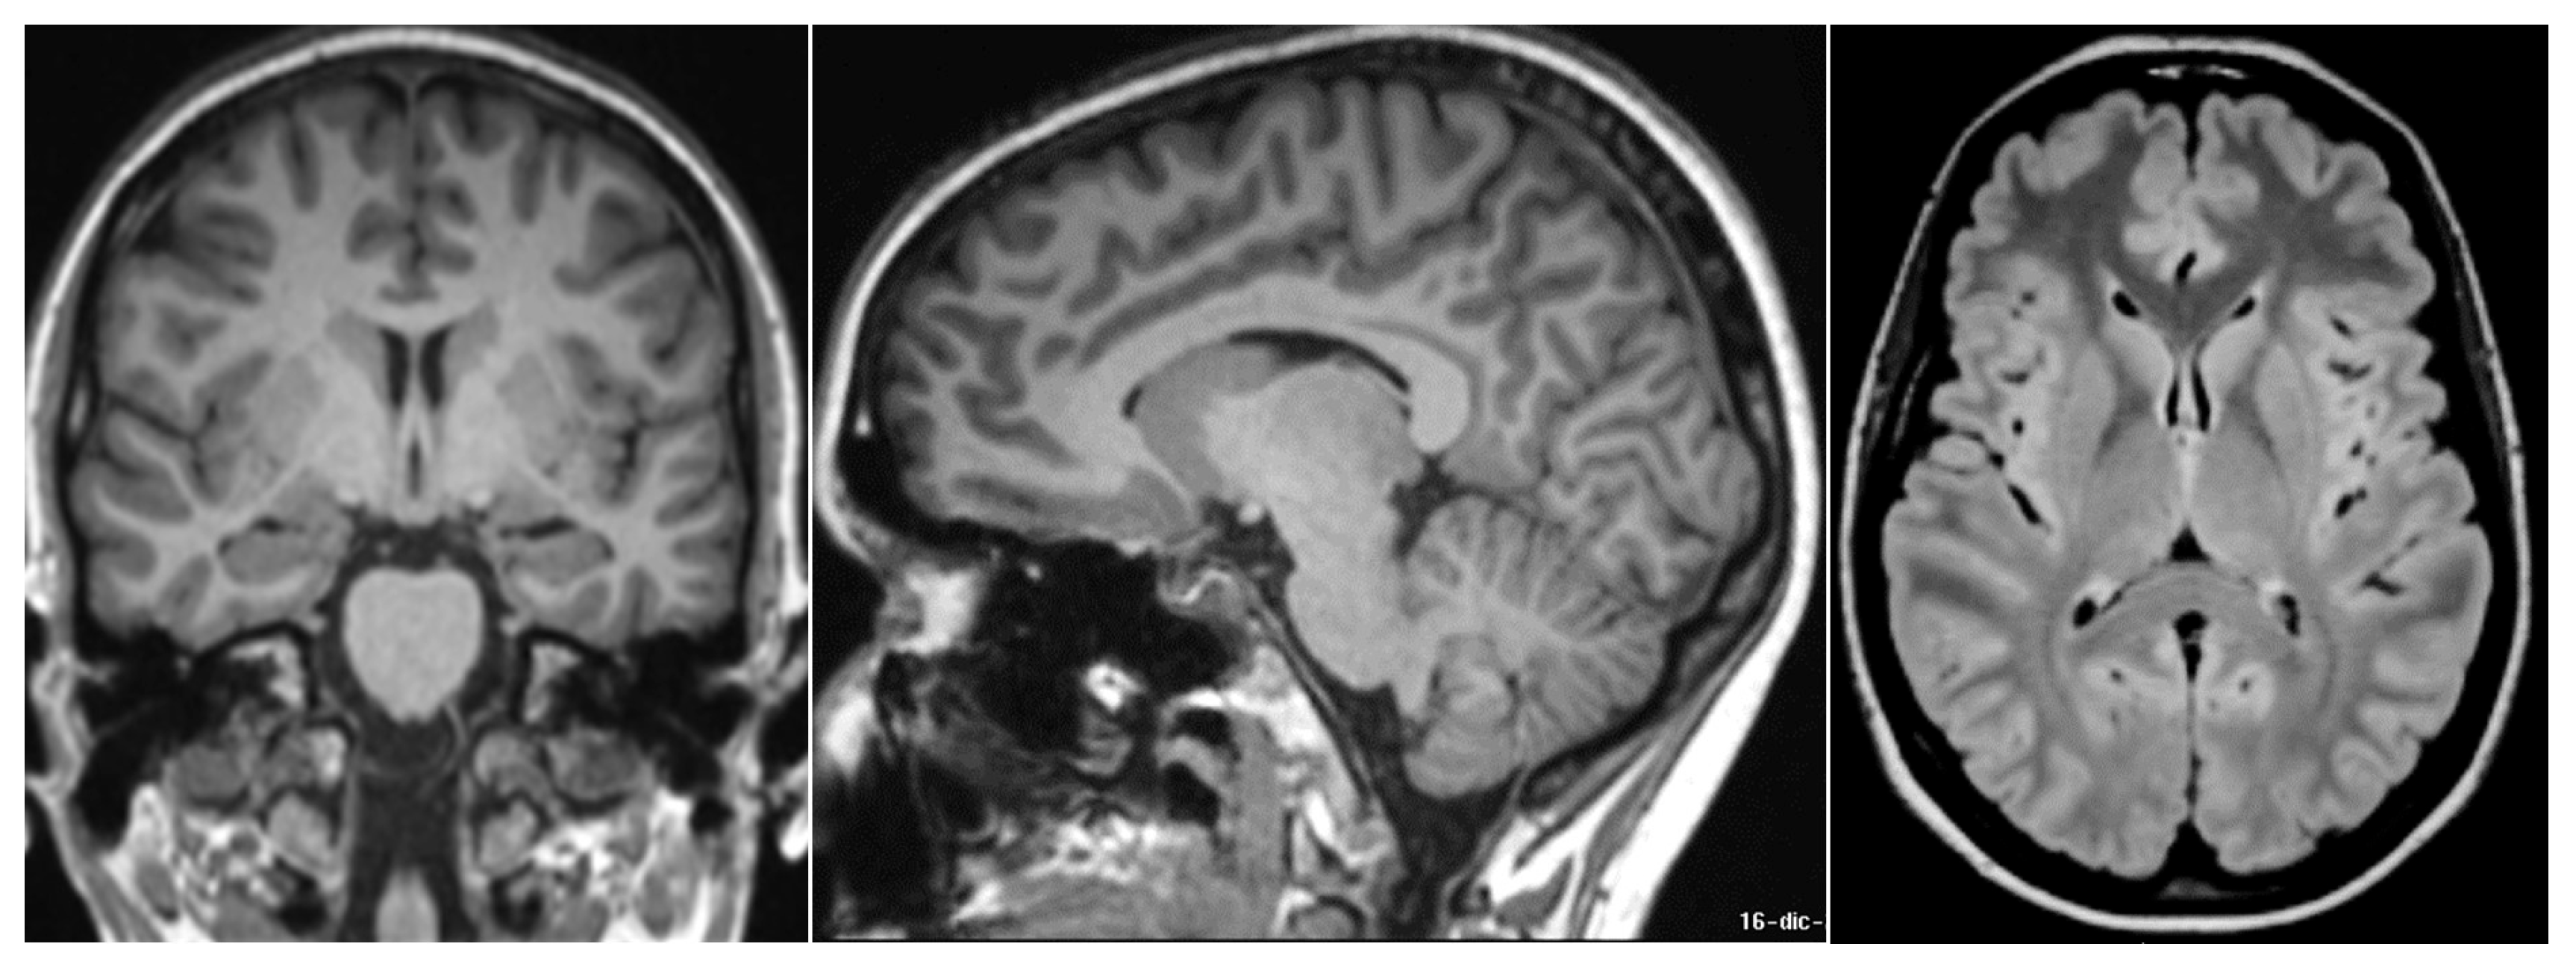

2. Case Description